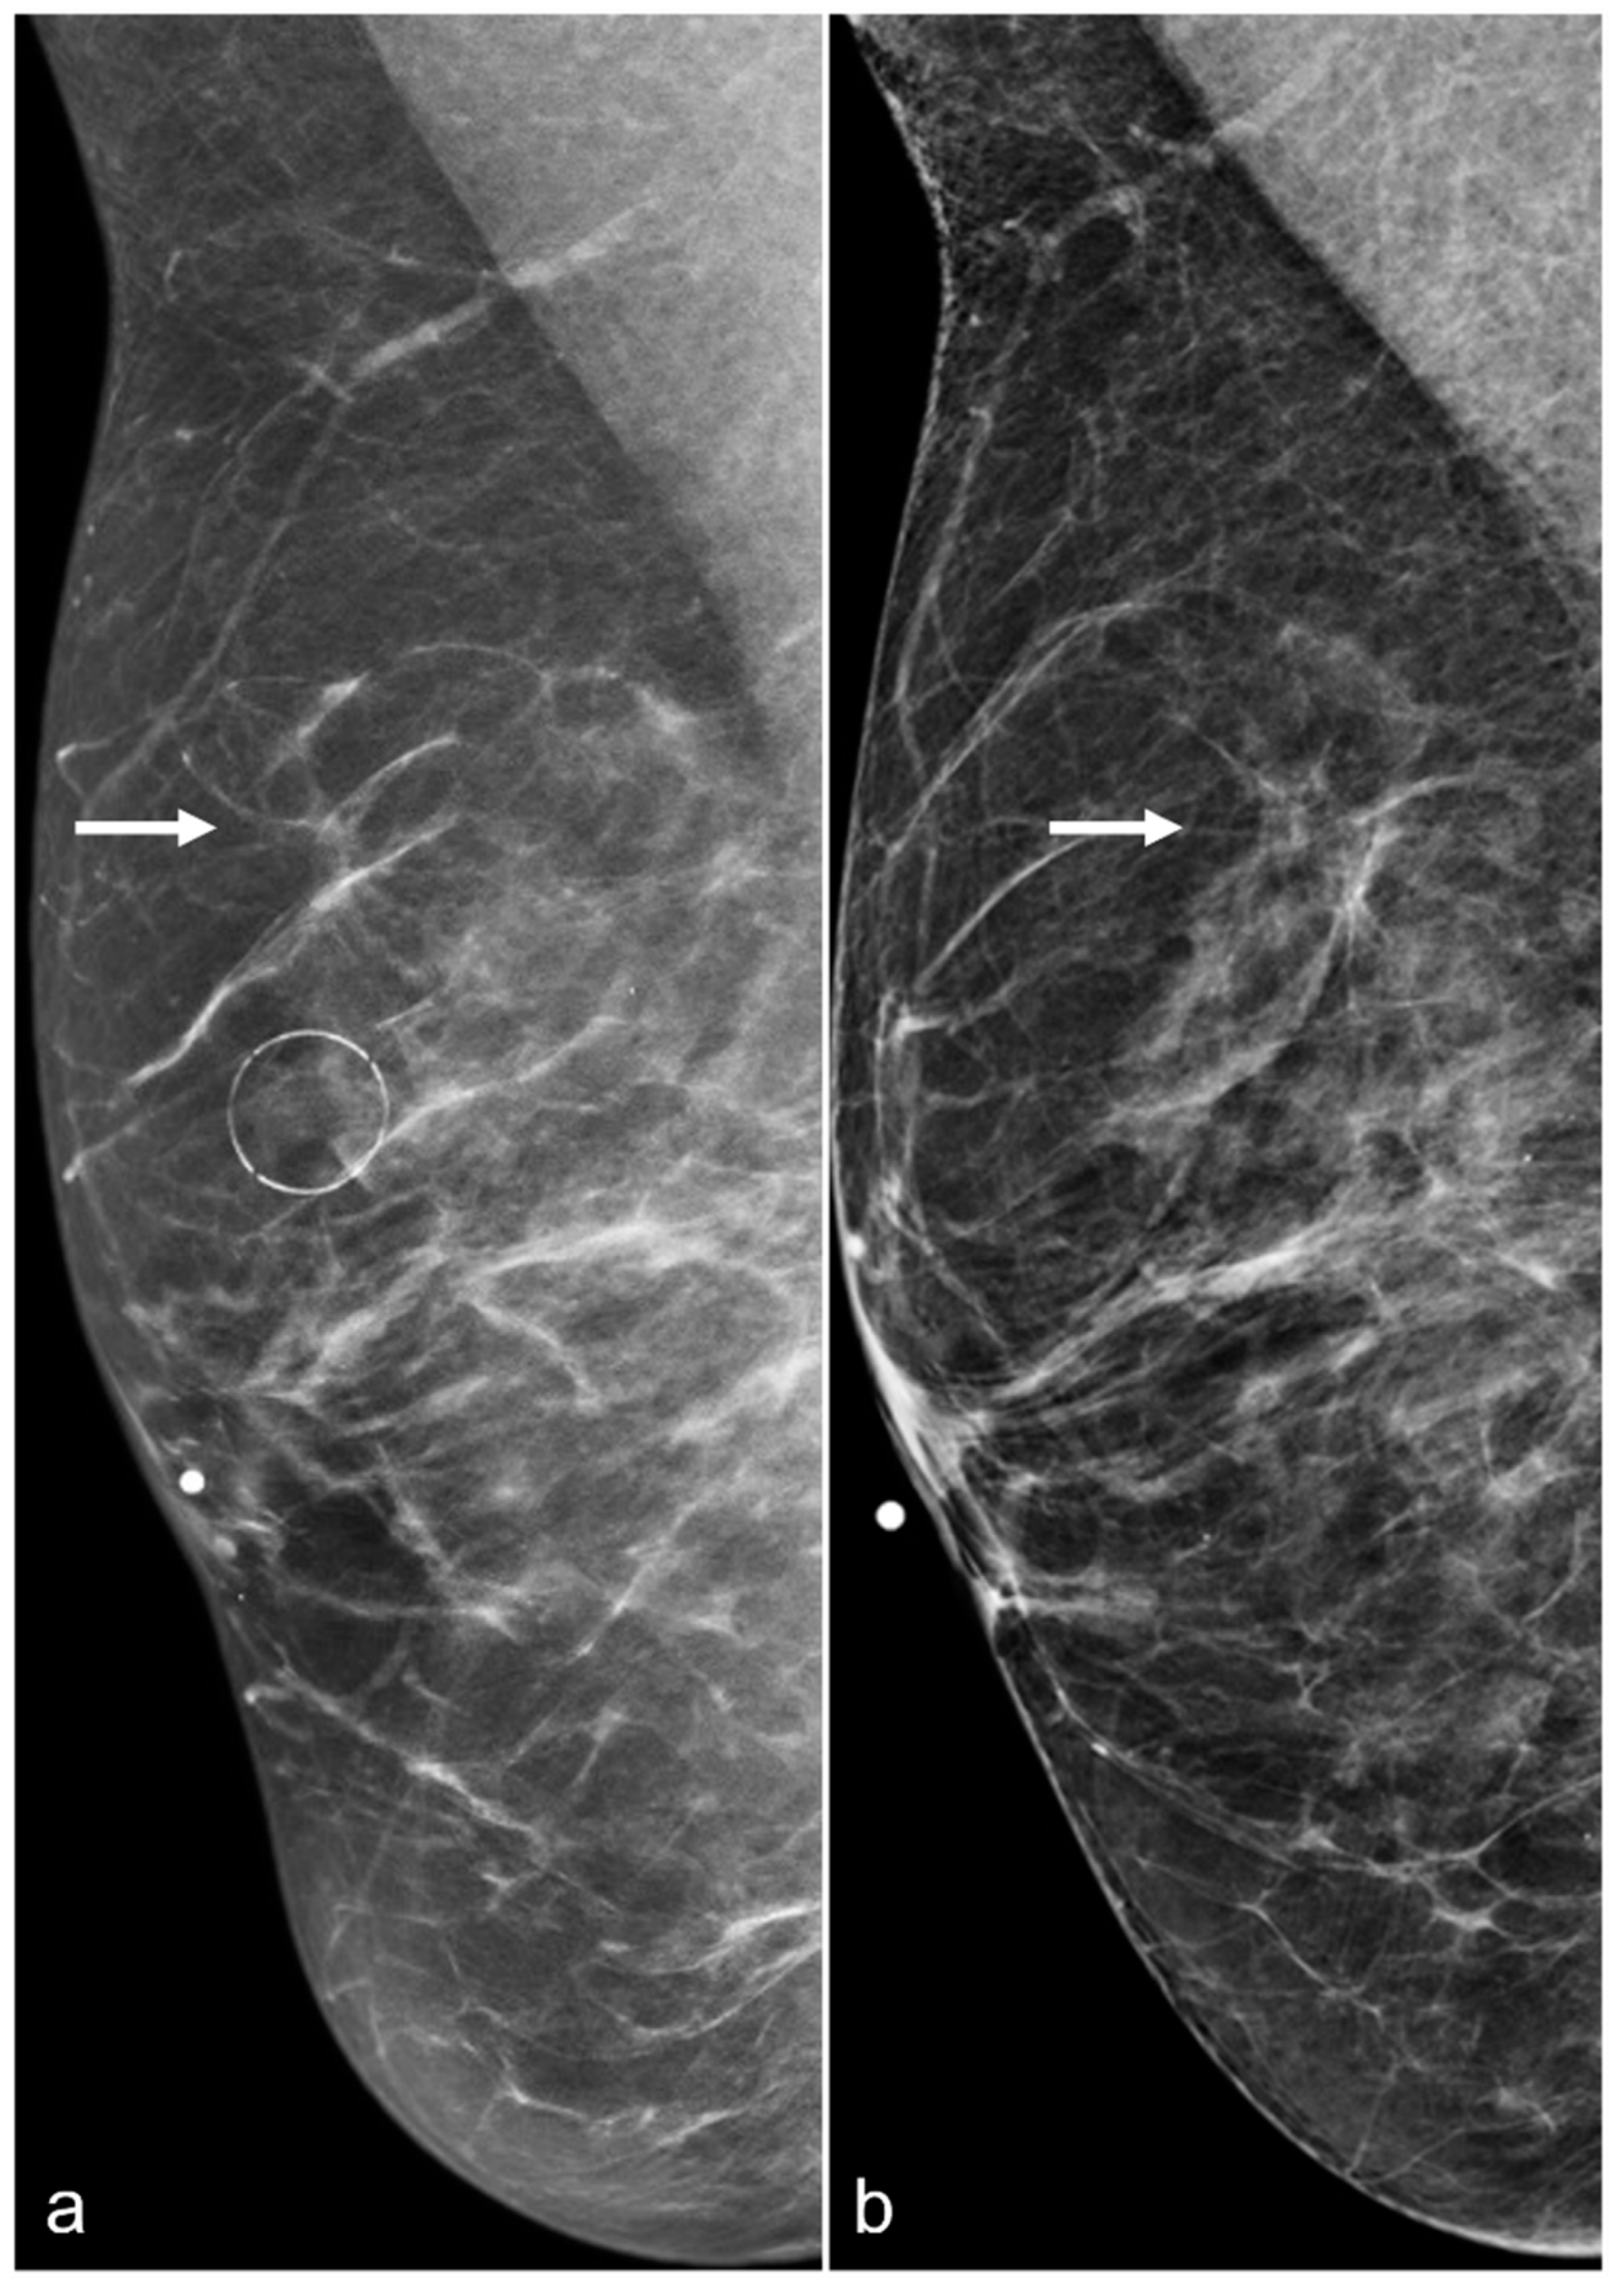

Figure 11. A 67-year-old woman with a history of subglandular silicone implants. Mammograms with bilateral CC (a) and MLO (b) views demonstrate curvilinear densities (arrows), consistent with residual implant capsules.